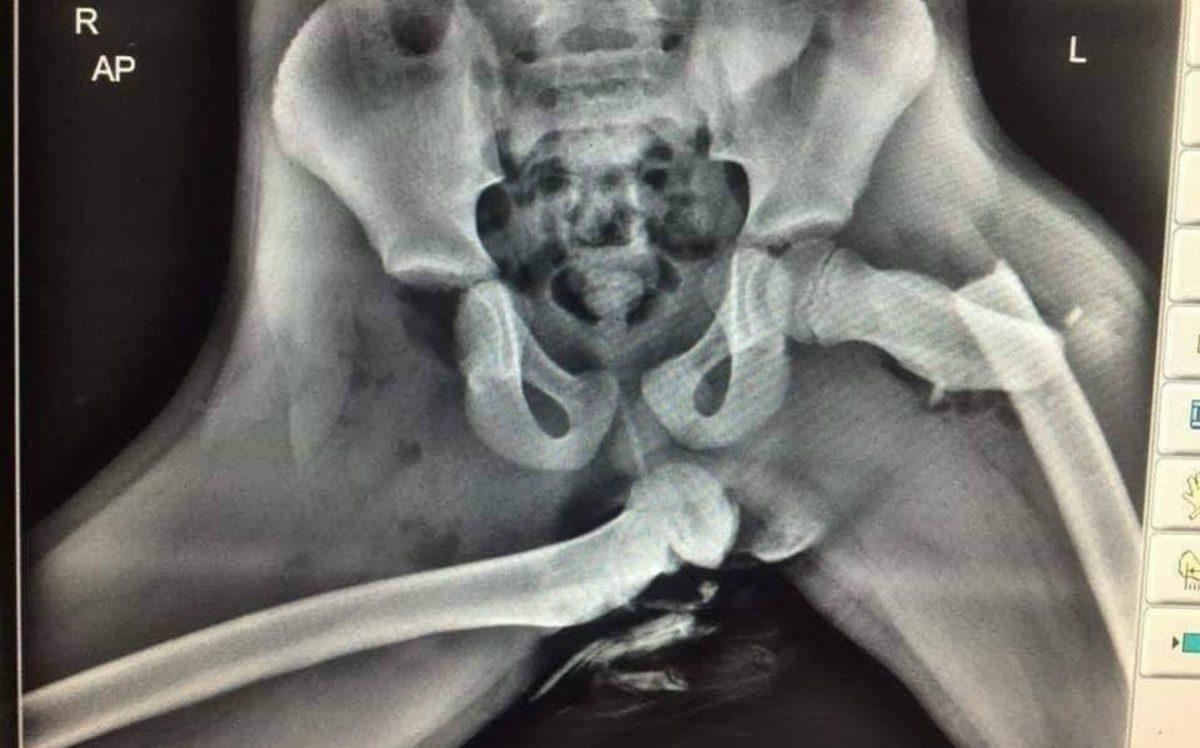

- Kaza sonrasında arabadan fırlayan bir adamın pelvis röntgeni.

Yedi yerinden kırılan pelvisinin, yerine oturtulabilmesi için çok sayıda vida ve harici bir sabitleme cihazı gerekmiş.

Emniyet kemerinizi takın!